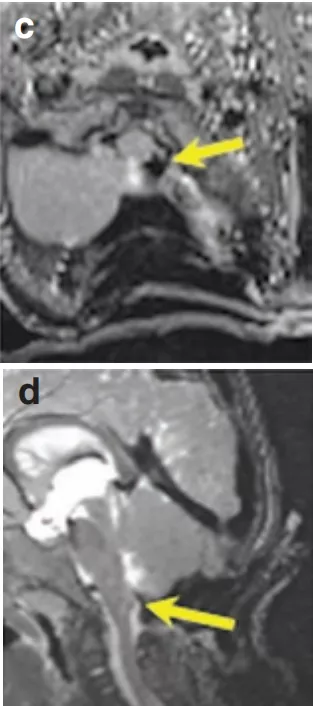

術中T1和T2MR(c和d)顯示腫瘤獲得全切,無任何腫瘤殘餘。